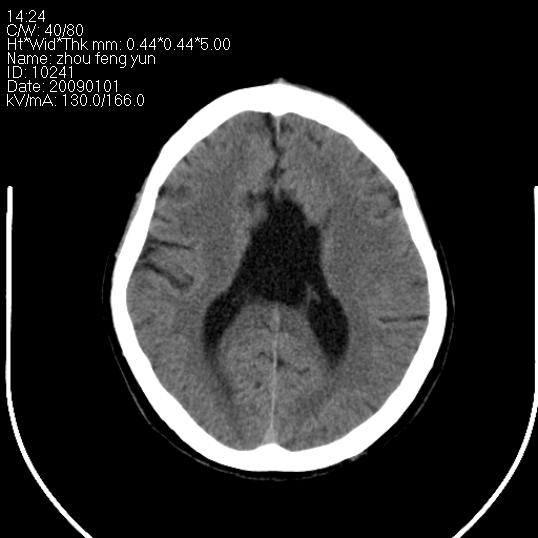

以下是引用hhcckk在2009-1-1 16:39:00的发言:[br]胼胝体嘴、膝部及部分体部发育不全,为囊状影替代,两侧侧脑室分离,脑室后角扩张[br][br]诊断:胼胝体发育不良[br][br]胼胝体发育不良(dysgenesis of the corpus callosum)是最常见的颅脑畸形,是胚胎期背部中线结构发育不良的一种形式。主要包括胼胝体缺如和部分缺如。胼胝体发育不良还可合并其他畸形,如胼胝体脂肪瘤、蛛网膜囊肿、脑膨出、chiari畸形、灰质异位症、脑回畸形等。[br][br]ct诊断要点:[br]1. ct横断扫描可见两侧侧脑室明显分离,脑室后角扩张,形成典型的蝙蝠翼状侧脑室外形。[br]2. 第三脑室扩大并向上插入两侧脑室体部之间,严重者第三脑室可上移到两侧大脑半球纵裂的顶部。在ct冠状扫描位显示更清。[br]4. 胼胝体畸形常伴有脂肪瘤,可测到其特征性脂肪密度。部分脂肪瘤的边缘可出现线样钙化[br]